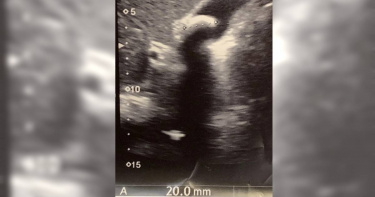

雖然許多人減肥都會推薦168斷食法,也就是把進食時間限縮在一天8小時內,剩餘16小時只喝水。但胃腸肝膽科醫師蕭敦仁也指出,一名藉由不吃早餐來實行168斷食的40歲女子,就是因為3年來長時間空腹讓膽汁無法排出,才養出2公分大的膽結石。醫師建議,健康的飲食方式為照3餐進食、有充足且含不飽和脂肪酸的好油脂,以降低膽結石風險。蕭敦仁醫師17日在臉書粉專發文指出,一位40歲女病患藉由168斷食法減肥,3年來成效不錯,但因為曾聽聞蕭敦仁在一次受訪時提到,「早餐不吃會增加2成膽結石風險」,女子擔心自己的膽恐出問題,「所以特地來做腹超,超音波一看,哇!有膽結石,而且2公分大,她很驚訝,怎麼會這樣?」對此,蕭敦仁也解釋,空腹時間長,膽汁不排出,本就會增加膽結石風險!因此「3餐都要吃,而且要有30%的油脂,最好是富含不飽和脂肪酸的好油!否則石頭會越養越大顆,到時就非開刀不可了!」至於不斷食如何控制體重呢?蕭敦仁則建議,可以3餐都吃7分飽的方式,控制總熱量的攝取,仍可達到減重效果,「為了減肥168要深思呀!!!」